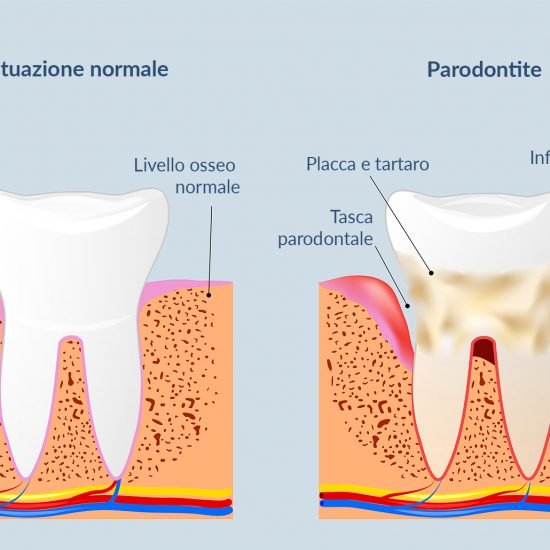

Patologie come la Parodontite, oggi più propriamente definita Malattia Parodontale, sono spesso asintomatiche fino al palesarsi di conseguenze irreversibili.

Dovete sapere che è possibile distinguere all’interno del cavo orale due grandi famiglie di batteri: i primi responsabili di problemi agli elementi dentali (carie), i secondi responsabili dei problemi gengivali (paradontite).

Non aspettate evidenze irreversibili, quali la mobilità dentale o la formazione di tasche gengivali purulente, rivolgetevi a Noi prima, passate per un controllo. E’ Gratis.